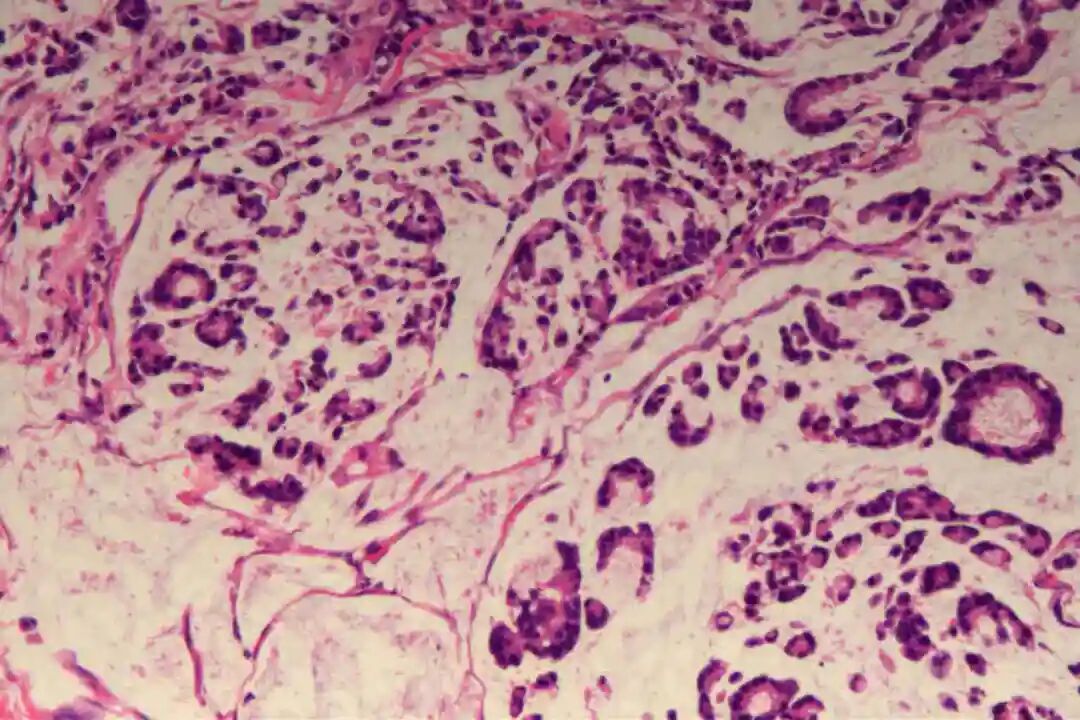

2.黏液腺癌基础特征:肿瘤细胞分泌大量细胞外黏液形成“黏液湖”,癌细胞漂浮其中或呈巢状、腺样排列,细胞核多为低 - 中级别,核分裂象低。

1. 形态学诊断:肿瘤组织含大量细胞外黏液,黏液成分占比通常>90%(单纯型),癌细胞呈小簇状、巢状漂浮于黏液湖中,B型乳腺黏液癌等可表现为细胞丰富伴神经内分泌形态(如胞质颗粒状)。